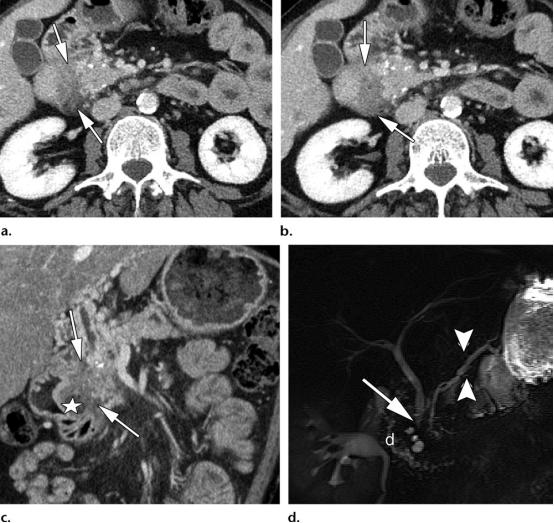

39岁男性,1型实性十二指肠旁胰腺炎(PDP,即沟槽性胰腺炎)

(a图,b图)轴位CT示边界不清的低密度肿物样病变,位于十二指肠胰腺沟内(白色长箭头),胰头区可见散在的胰腺实质钙化灶。

(c图)冠状位CT图示十二指肠沟内肿物样病变(白色长箭头),以及十二指肠壁的囊性变(白色五角星),胆总管远端部分可见。

(d图)磁共振胆胰管成像示胆总管远端局灶狭窄(白色长箭头),胰腺分支胰管略微显著(白色短箭头),关注视察十二指肠胰腺沟的增宽,以及十二指肠壁的囊性变(白色字母d)。